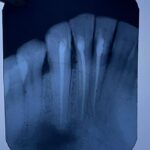

- Case of Radicular cyst done by surgical periapical curettage followed by apicocetomy. A multidisciplinary approach involving maxillofacial surgery and Endodontics expertise. Case done by Dr. Harmurti Singh (AP), Dr. Himi Rathore (SR) and Dr. Akhil Trivedi (SR).